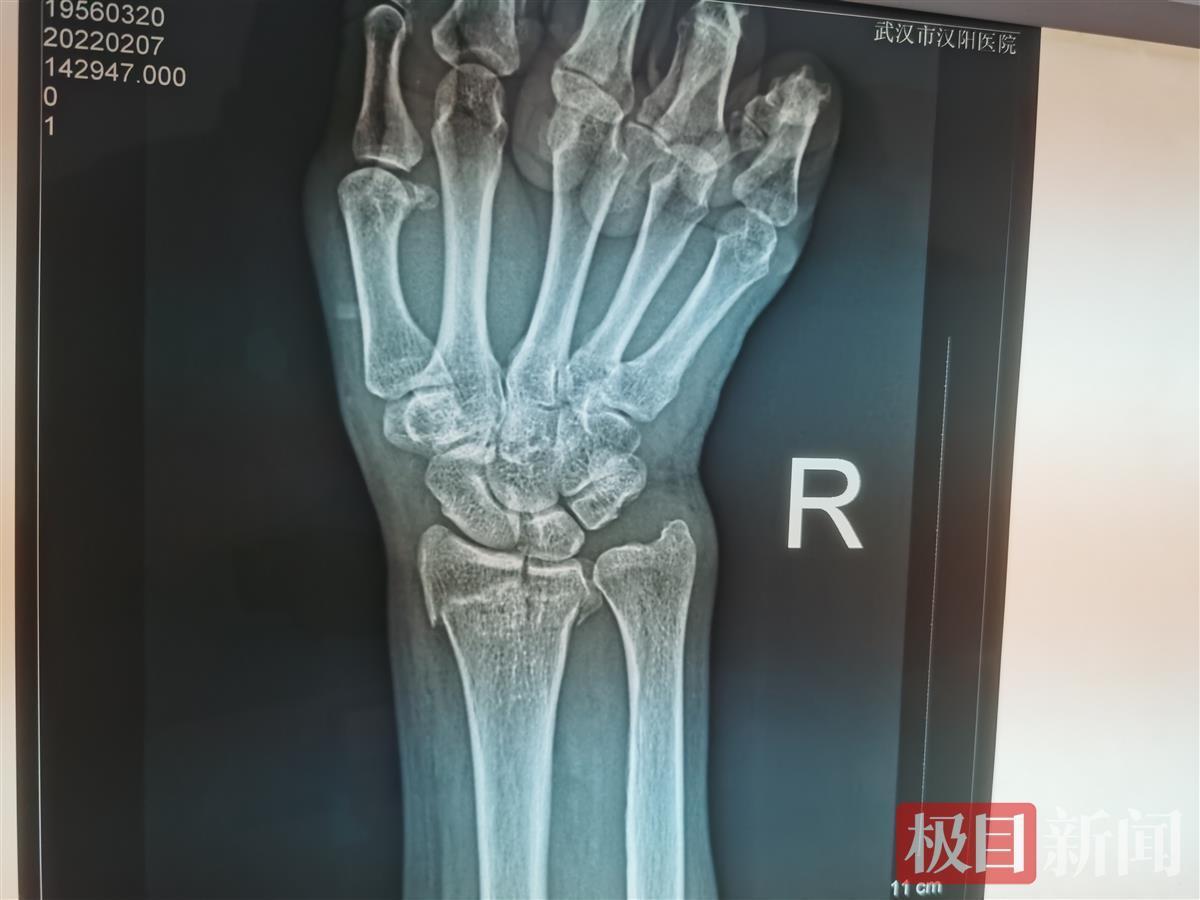

王女士说,她早上7点出门,因担心上班迟到,一路小跑去拿车,没想到踩到一块光面的地砖,突然脚底一滑,人重重摔倒在地。出于本能反应,摔倒时她右手撑地,本以为没啥事。直到下午,手腕疼痛、肿胀、活动受限,于是赶到医院检查。拍片后,该院骨科医生罗建业诊断是桡骨远端骨折合并尺骨茎突骨折,为其手部打石膏,并叮嘱多休息。

无独有偶,下午4时许,又一位63岁的患者就诊,同样也是手腕部受伤。该患者说,她是汉阳一小区的保洁人员,7日清晨打扫地面积雪时脚下一滑,突然侧身摔了下去,虽然当时有点疼,但也没在意,抹了一点药。直到下午,右手肿得厉害,鼓起核桃大的包块,还有淤青,手腕动弹不了,这才来医院就诊。拍片结果显示,患者右侧桡骨粉碎性骨科,石膏固定效果欠佳,为保证愈后效果,建议住院行支架外固定手术,预计一周之内即可康复出院。